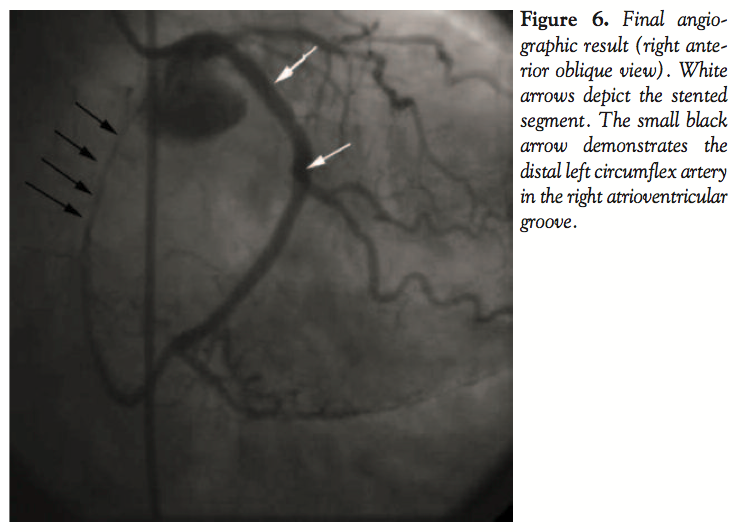

The patient was administered 325 mg of oral aspirin and intravenous (IV) unfractionated heparin (50 IV/kg bolus) and intravenous abciximab (0.25 mg/kg bolus and IV infusion of 0.125/kg/min). A 6-French EBU guide catheter (Medtronic Vascular Inc., Minneapolis, Minnesota) engaged the left coronary artery and a 0.014 BMW wire (Abbott Vascular, Santa Clara, California) was advanced across the lesion without difficulty. Manual aspiration thrombectomy was performed using an Export catheter (Medtronic Vascular Inc.). This yielded a large amount of red and white thrombotic material, associated with improvement in the subsequent angiographic appearance of the vessel. No additional macrovascular embolization was identified. Stenting was performed using a 3.5 x 23 mm Cypher stent (Cordis Corp., Miami Lakes, Florida). The successful final angiographic result is shown in Figure 6. Prior to sheath removal, left ventriculography demonstrated an ejection

50%. A 75% lesion in a small caliber first diagonal branch was noted. A critical (> 90%) narrowing in the proximal portion of the left circumflex artery (LCX) was present. This lesion demonstrated a large, hazy filling defect consistent with intracoronary thrombus. Angiographic cutoff of the posterior-lateral vessel suggested distal embolization of thrombus (Figures 4 and 5). The LCX continued along the atrioventricular groove, giving off posterior left ventricular and posterior descending (PDA) branches. The vessel then continued beyond the PDA, following the

course of the right atrioventricular groove in the typical distribution of the right coronary artery (RCA) and provided multiple right ventricular marginal branches.